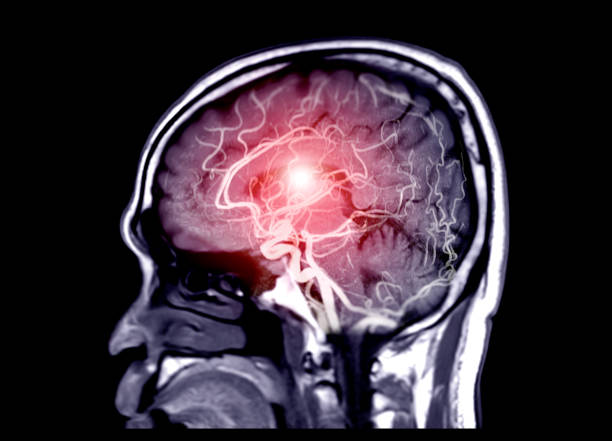

Cette maladie, qui se caractérise par la formation d’un caillot de sang, est une affection responsable des trois principales maladies cardiovasculaires mortelles dans le monde : la crise cardiaque, l’ AVC et la thromboembolie veineuse.